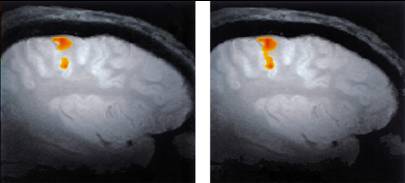

Auditory Function

• Functional MRI scan shows the auditory cortex is activated in patients who hallucinate (hear voices).